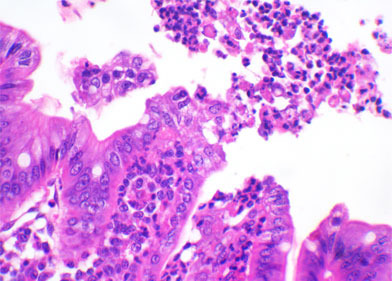

在上一篇文章中,我们提到肠道组织学能检测出可能的病原体,并且在某些病例中能确定是哪种病原体。例如,球虫、轮状病毒、TGEv、PEDv 、新型冠状病毒 、产气荚膜梭菌A型都会引起肠绒毛萎缩。如果采集的仔猪肠道样品放置超过5-6天,那么肠绒毛细胞质中就会有有性/无性生殖球虫 。如果没有球虫,就要用免疫组织化学检测轮状病毒/冠状病毒以确定肠道病原体。组织学检测产肠毒素大肠杆菌(ETEC)病发现:无数的甲球杆菌粘附在肠上皮细胞绒毛表面或外侧部(几乎存在于所有样品中)。产气荚膜杆菌C型会引起小肠肿胀出血。艰难梭菌是唯一一个能引起大肠病变的病原体。它常引起结肠水肿。艰难梭菌病的主要症状是:杯状细胞减少和结肠粘膜中性粒细胞渗透性加强(有时候会像火山爆发一样冲破上皮细胞膜)。最难用组织学方法诊断的病原是产气荚膜梭菌A型,它能引起肠绒毛萎缩,但是即使没有这种病变,也不能排除与它无关的可能性。

| 轮状病毒 | 产气荚膜梭菌 | 大肠杆菌 |